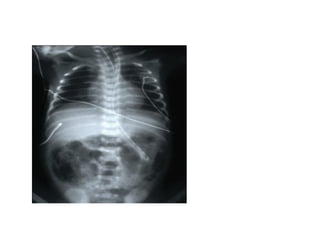

imaging

• Multiple gas filled loops of intestine

• Pneumatosis intestinalisc: pathognomonic for

NEC

• a collection of cystic or linear lucencies in the

bowel wall,

• Frequency may reach 19-98%but may be

absent in upto 14% of cases of NEC

imaging • Multiple gasfilled loops of intestine • Pneumatosis intestinalisc: pathognomonic for NEC • a collection of cystic or linear lucencies in the bowel wall, • Frequency may reach 19-98%but may be absent in upto 14% of cases of NEC

• 25.

• Portal venousgas: linear branching radiolucencies overlying the liver and often extending to its periphery • incidence of 10% to 30%.poor prognosis • Pneumoperitoneum: in 12-30% of patients • Best seen on lateral decubitus film • Football sign, double wall sign, • Only 63% of patients with perforation show the xray sign

• 26.

• Intraperitoneal fluid:gasless abdomen, flank opacity, separation of bowel loops • Persistent dilated bowel loop: dilated bowel loop remained unchanged for 24 to 36 hours